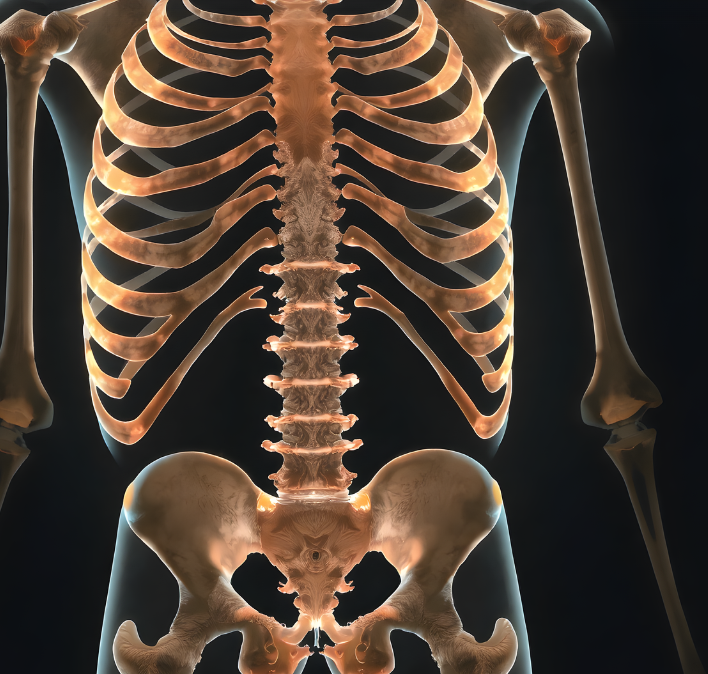

🔎 골다공증이 위험한 이유

- 초기 증상이 거의 없어 진단이 늦어질 가능성이 큼

- 척추뼈, 손목, 고관절 골절 위험 증가

- 일상생활 중 작은 충격에도 골절이 발생할 수 있음

- 심한 경우 허리뼈가 무너져 압박골절이 생길 수도 있음